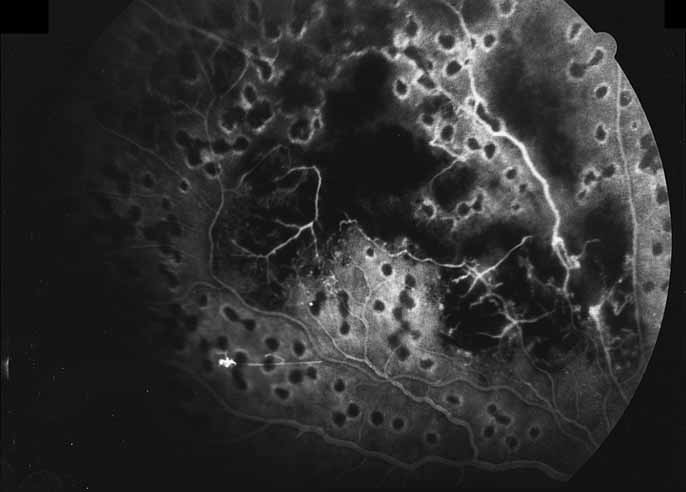

A variety of inflammations and infections, most notably presumed ocular histoplasmosis syndrome (see Figs. 37 and 38), serpiginous choroiditis, and multifocal choroiditis (see Figs. 39, 40, 41, and 42),1,89,90 are associated with the late complication of choroidal neovascularization. Probably the single most important application of fluorescein angiography in infectious and inflammatory diseases of the posterior segment is for the evaluation and potential treatment of this complication. In some instances, fluorescein angiography may be the single best method to determine whether visual loss seen late in the course of such disease as paramacular toxoplasmosis or serpiginous choroiditis is the result of secondary choroidal neovascularization or inflammatory disease recrudescence. In other diseases, such as presumed ocular histoplasmosis syndrome or multifocal choroiditis, choroidal neovascularization may occur early and be suspected on the basis of associated hemorrhage or lipid exudation. In some instances, even with the benefit of high-quality fluorescein angiography it may be difficult to distinguish between choroidal vasculitis and choroidal neovascularization superimposed on underlying choroiditis. We have recently identified a subgroup of young female patients, frequently darkly pigmented, who develop solitary zones of elevated choroiditis that have features of choroidal neovascularization. These appear to have a more indolent course than either idiopathic choroidal neovascularization or that associated with atypical multifocal choroiditis.

Fig. 41 Multifocal choroiditis. Color photograph shows multiple small choroidal lesions scattered throughout the posterior pole.

Fig. 42 Multifocal choroiditis. ICG angiography shows multiple hypofluorescent spots in the distribution of the choroidal lesions seen on color photography.